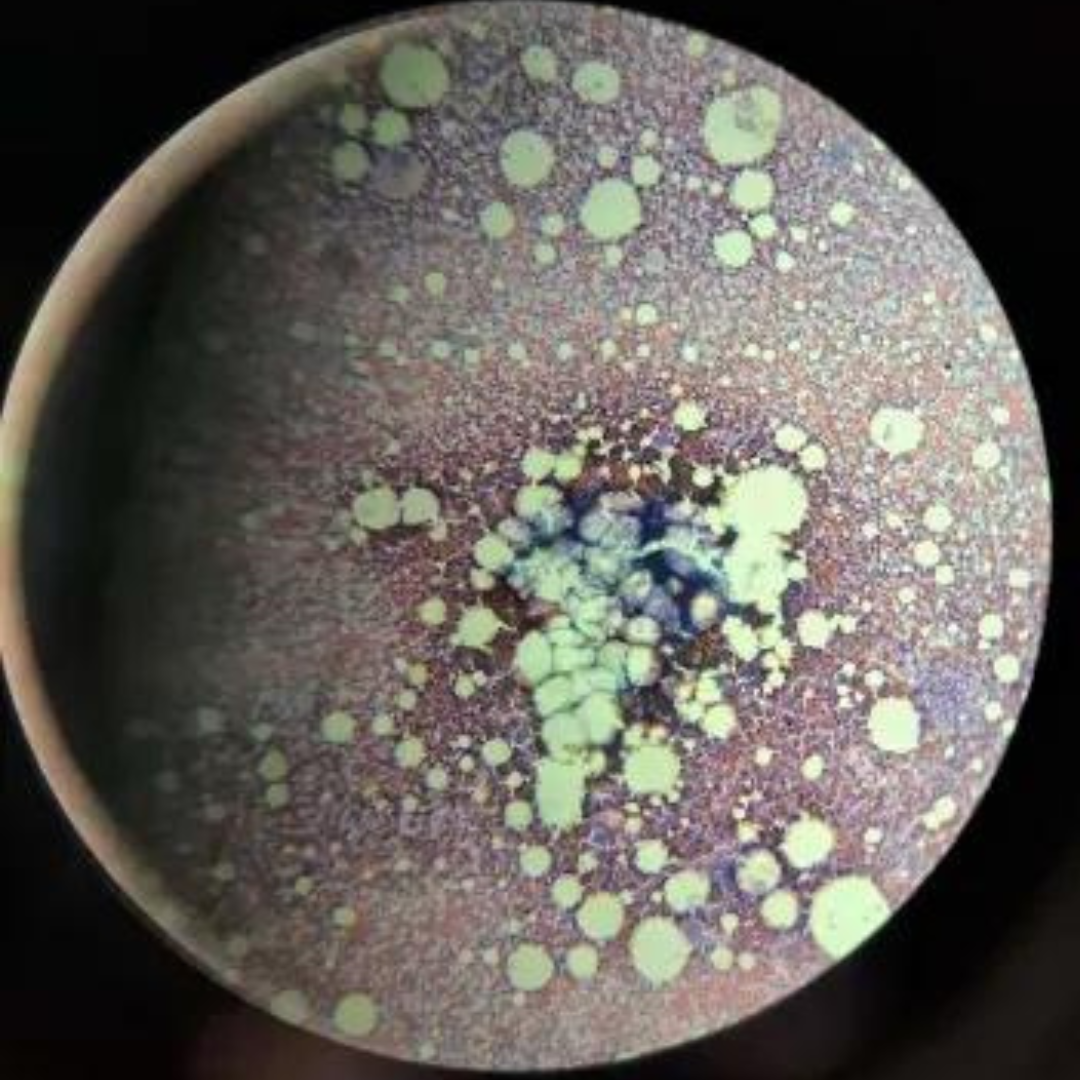

New cards

Bone Marrow

6

New cards

Bone Marrow

7

New cards

Bone Marrow